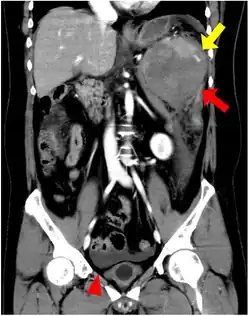

An accessory spleen is a small nodule of splenic tissue found apart from the main body of the spleen. Accessory spleens are found in approximately 10 percent of the population[1] and are typically around 1 centimeter in diameter. They may resemble a lymph node or a small spleen. They form either by the result of developmental anomalies or trauma.[2] They are medically significant in that they may result in interpretation errors in diagnostic imaging[2] or continued symptoms after therapeutic splenectomy.[1] Polysplenia is the presence of multiple accessory spleens rather than one normal spleen.

If splenectomy is performed for conditions in which blood cells are sequestered in the spleen, failure to remove accessory spleens may result in the failure of the condition to resolve.[1] During medical imaging, accessory spleens may be confused for enlarged lymph nodes or neoplastic growth in the tail of the pancreas,[5] gastrointestinal tract, adrenal glands or gonads.[2]